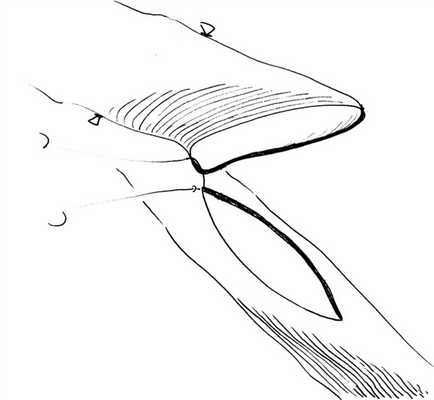

Шить анастомоз мы начинаем с «пятки», фиксация и низведение кондуита на первый шов с узлом (рис. 1), Рис. 1. Фиксация «пятки» коронарного анастомоза. с последующим непрерывным обвивным швом по всей окружности анастомоза. Ассистент «ведет» нитку и держит ее в натяжении между стежками, но при этом очень деликатно, не повреждая и не заламывая ее.

Для наложения анастомозов рекомендуем короткую (около 10,0 см) полипропиленовую нить 8/0 с иглой 6,5 мм, в отдельных случаях допустимо использовать полипропиленовую нить 9/0 на игле 5,0 мм.